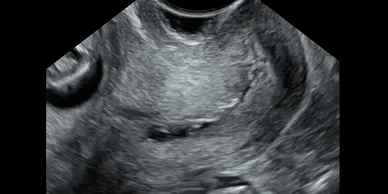

Skanda Advanced Ultrasound Scan Centre starts right from the onset of pregnancy. Our Fetal Medicine experts are concerned with the health of the fetus at every stage – monitoring growth & development; predicting, detecting & managing any complications; and treating congenital disorders & anomalies in the womb itself.